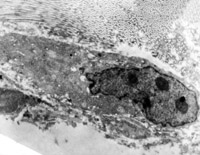

5-2-5 傷后第5天,膠原纖維相互融合,其間的細(xì)胞已崩解  TEM×6000